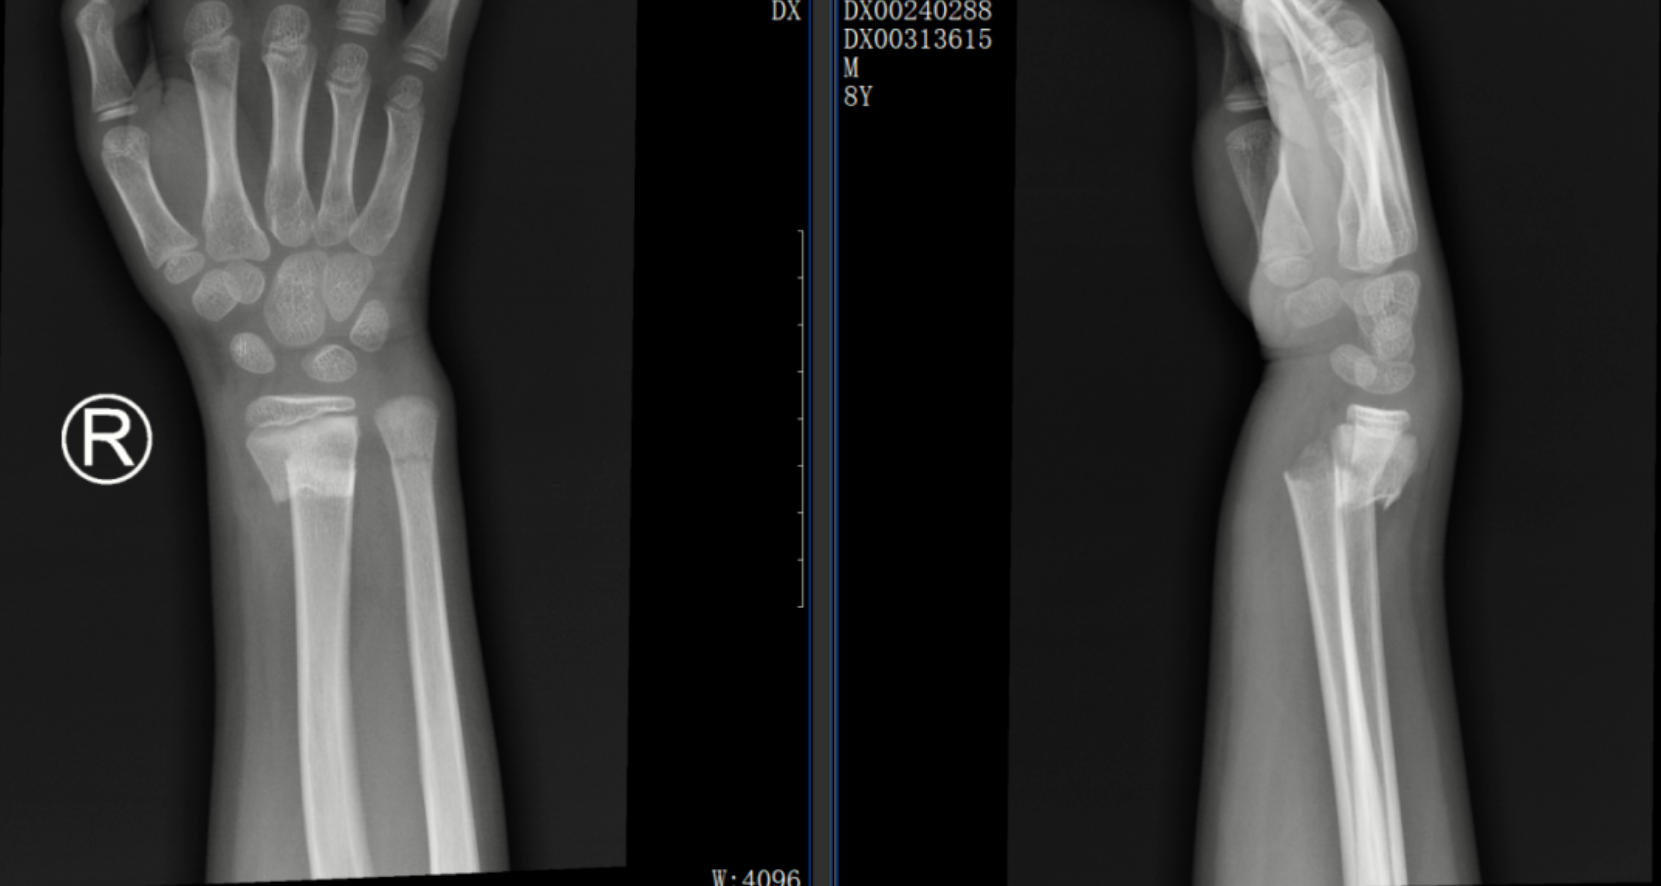

一位 8歲的學(xué)生在上學(xué)途中不慎摔傷,造成尺橈骨遠(yuǎn)端骨折。家屬心急如焚,為保守治療來到了我院中醫(yī)正骨中心就診。中醫(yī)正骨醫(yī)師運(yùn)用精湛的手法為小朋友進(jìn)行了復(fù)位,并配合夾板固定。3 周后骨痂形成,小朋友的功能活動也恢復(fù)良好。這一案例,讓家其屬深刻體會到了中醫(yī)正骨的獨(dú)特魅力。

正骨前后影像資料